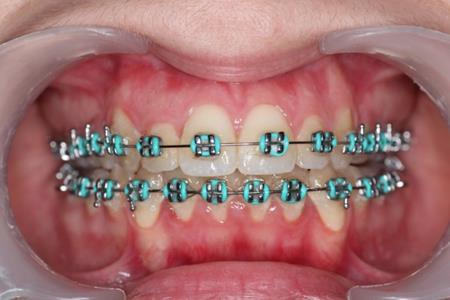

Figure 5.Intraoral photography after the mini-implant activation

Figure 7.Clinical situation after intrusion with orthodontic implants.

After treatment the patient had a normal overbite and overjet and a stable occlusion, a class I canine and molar relationship.